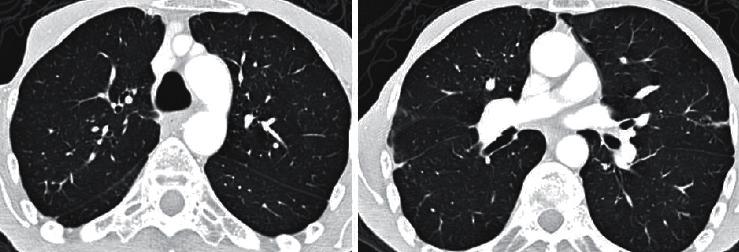

Pulmonary apical fibrosis is a rare complication of ankylosing spondylitis (AS). The essential characteristics of this lesion are its very slow progression and frequently asymptomatic nature. Herein, we are presenting a patient with AS who rapidly developed pulmonary apical fibrosis in a 3-year period despite decreased musculoskeletal pains. The 60-year-old male applied with complaints of progressively increasing cough in the recent two years, dyspnea, and fatigue. He had no chronic disease except AS. He had no continuous medication except nonsteroid anti-inflammatory drugs for 2-3 days monthly since his musculoskeletal pains decreased in the recent years. His physical examination revealed reduced breath sounds in the upper zones of the right lung. Chest X-ray revealed increased diffuse opacity in the upper zones of the right lung. Thoracic high-resolution computed tomography showed a consolidation accompanied with traction bronchiectases compatible with chronic fibrosis in the upper lobe of the right lung. However, thoracic computed tomography of the patient performed 3 years ago did not reveal pulmonary apical fibrosis and parenchymal destruction. Biopsy revealed no finding of malignancy, granulomatous inflammation, or vasculitis. The results of cultures were negative. So, the patient was diagnosed as pulmonary involvement of AS, which developed in a 3-year period. This case has shown that extra-articular complications may continue to develop in patients with AS even if their musculoskeletal complaints have subsided. So, patients with AS should be followed up regularly with systemic examinations.

肺尖纤维化是强直性脊柱炎(AS)的一种罕见并发症。该病变的基本特征是进展非常缓慢且通常无症状。在此,我们报告一名AS患者,尽管其肌肉骨骼疼痛减轻,但在3年内迅速发展为肺尖纤维化。这位60岁男性因近两年来咳嗽逐渐加重、呼吸困难和疲劳前来就诊。除AS外,他无其他慢性疾病。由于近年来肌肉骨骼疼痛减轻,他除了每月服用2 - 3天的非甾体抗炎药外,没有持续用药。体格检查发现右肺上叶呼吸音减弱。胸部X线显示右肺上叶弥漫性模糊影增加。胸部高分辨率计算机断层扫描显示右肺上叶有实变,并伴有与慢性纤维化相符的牵拉性支气管扩张。然而,该患者3年前的胸部计算机断层扫描未显示肺尖纤维化和实质破坏。活检未发现恶性肿瘤、肉芽肿性炎症或血管炎。培养结果为阴性。因此,该患者被诊断为3年内发生的AS肺部受累。该病例表明,即使AS患者的肌肉骨骼症状已缓解,其关节外并发症仍可能继续发展。所以,AS患者应定期进行全身检查随访。